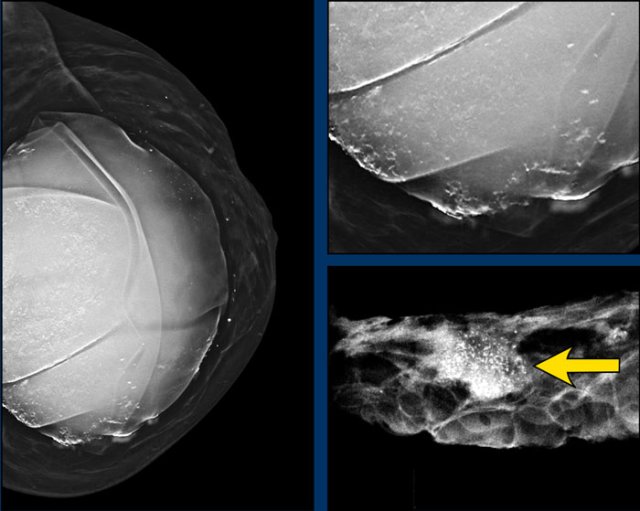

On this mammogram there were both capsular calcifications and atypical extracapsular calcifications.

Detail of the specimen showing mass and grouped calcifications.

Pathology: breast cancer grade 2, no special type (NST).

Typical appearance of silicone outside of the capsule presenting as dense well deliniated masses outside the contour of the breast implant.

Silicone granulomas

Silicone granulomas remainig after removal of breast implant because of previous extracapsular rupture in 2013.

Silicone granulomas can manifest as masses with suspicious morphology and enhancement dynamics on breast MRI or with increased FDG uptake on PET CT.

They

can present at the periphery of the prosthesis or in breast tissue after

rupture.

The presence of silicone implants and awareness of the possibility of a rupture and formation of silicone granulomas may help in facilitating a correct diagnosis (ref).